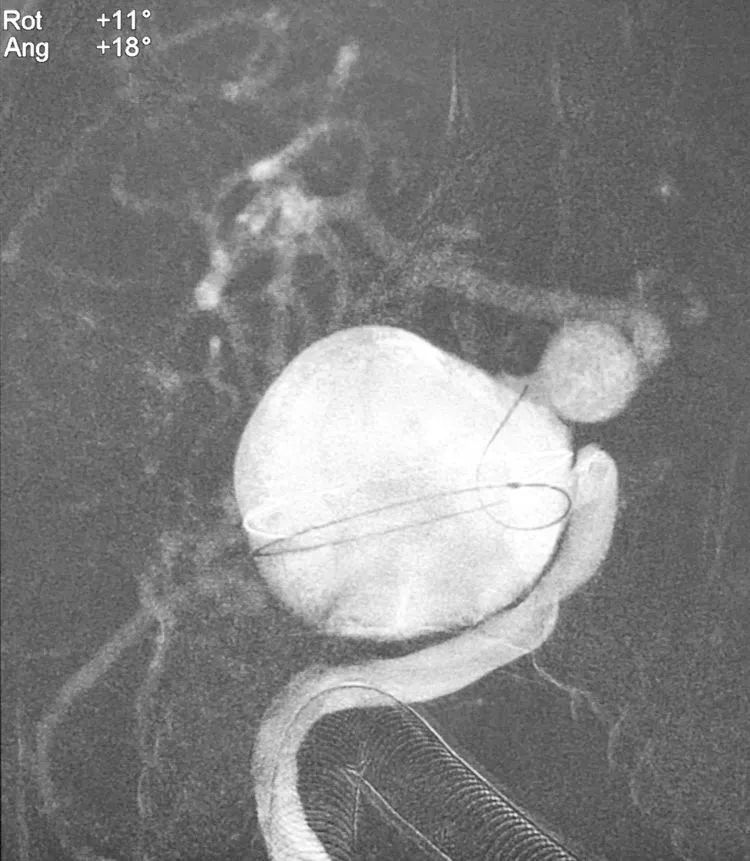

计划不如变化,决定一期先用弹簧圈填塞大瘤,隔至少一个月后再二期置放密网支架。双微管依次、交替填入11枚弹簧圈(MicroPlex 18-24-68-Cosmos Complex 九枚,MicroPlex 18-20-65-Cosmos Complex,QC-20-50-3D),部分栓塞大瘤。

术后右颈内动脉各角度造影显示大瘤部分栓塞,载瘤动脉畅通,希望通过一段时间的血流冲击使大瘤内的弹簧圈夯实,为二期支架导管的通过提供铺垫和支撑。